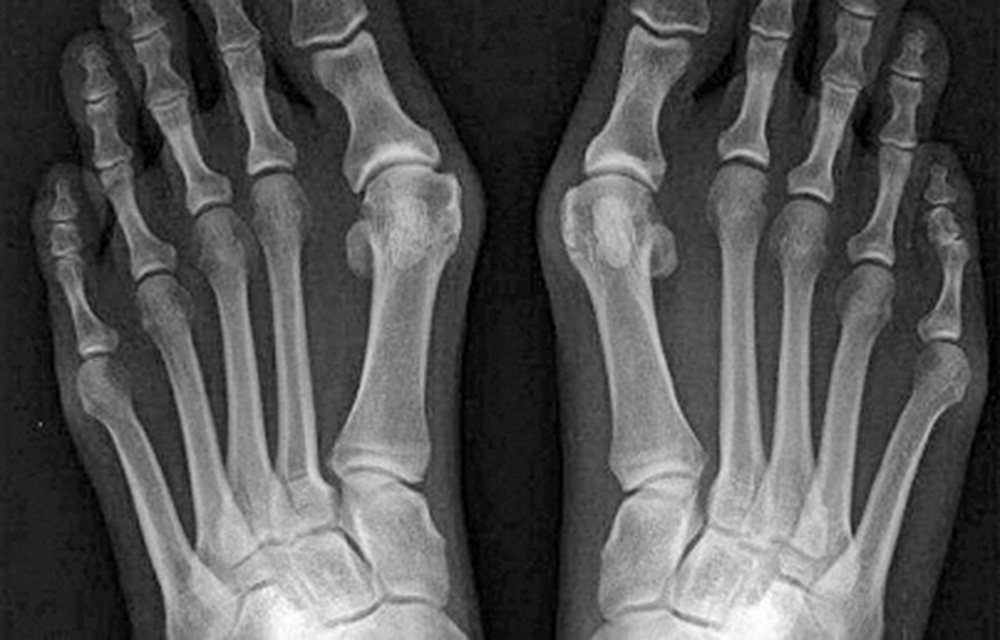

La articulación que se afecta con mayor frecuencia es la tarsometatarsiana, siendo bilateral en un 20 por ciento de los casos, además si el trastorno progresa con rapidez, la articulación se vuelve extremadamente dolorosa.

Para confirmar el padecimiento los médicos pueden utilizar una radiografía para detectar la presencia de una posible lesión articular, también pueden ayudarse de la ecografía y la gammagrafía. Además entre más pronto se detecte la enfermedad, los médicos podrán cambiar el curso de la enfermedad.